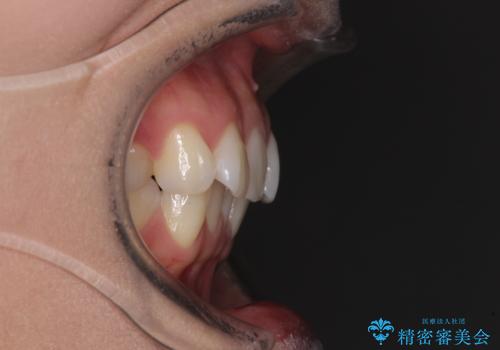

前歯のデコボコを解消 インビザラインの矯正治療

- 前歯のデコボコを治したいとのことで来院された患者様です。

上下顎ともに歯列全体の後方移動とIPR(歯と歯の間を削る)によってデコボコが解消するように設計し、インビザラインにより治療を行うこととしました。

上下ともにIPRを積極的に行っているため、舌の突出癖をしっかりと改善できないと、後戻りにより隙間やデコボコが早い段階で発現することになるため、舌のトレーニングが非常に大切になります。